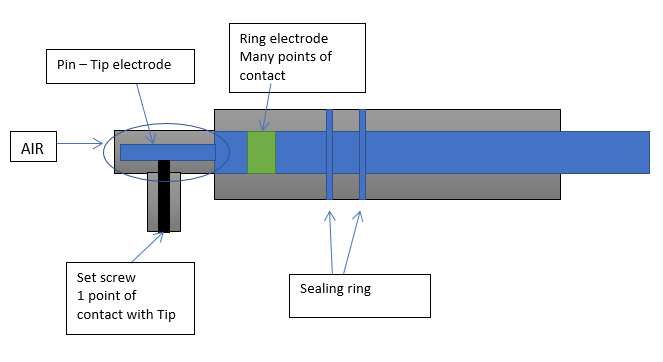

A 32-year-old male presented with an out of hospital cardiac arrest and underwent implantation of a secondary prevention subcutaneous implantable cardiac defibrillator (S-ICD). The implant procedure was performed under general anaesthetic and was uncomplicated, with the secondary sensing configuration (lead tip to can) selected by the automatic device set up. The system integrity was confirmed with a defibrillation threshold test. Ventricular fibrillation (VF), was successfully induced and treated appropriately with a single 65 joule shock, recording a satisfactory shock impedance.